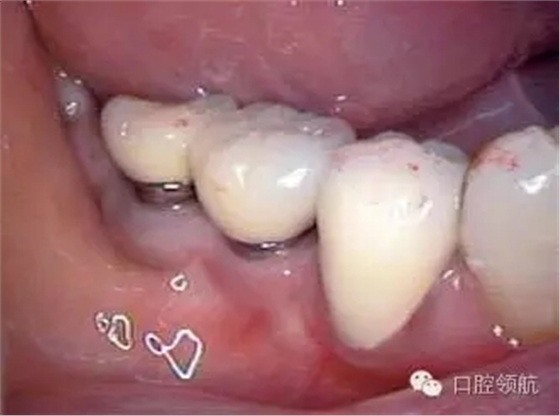

患者, 5 3 歲, 女, 2 0 0 2 年2 月(右下第6、7顆牙) 接受種植治療,采用了一次手術的方法,SwissPlus種植體(Zimmer公司,直徑3.7mm×長徑10.00mm),6個月后取印模,制作混合陶瓷上部修復體(圖1)。

圖1 上部修復體安裝后的口內照片